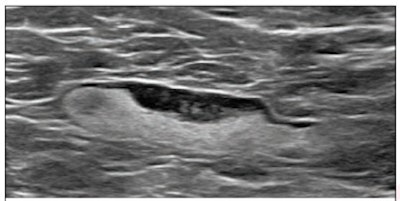

(Above) 55-year-old woman who underwent screening mammogram and ultrasound seven days after first COVID-19 vaccination dose. Screening mammogram and US demonstrated unilateral left axillary lymph node with cortical thickness of 5 mm on ultrasound (not shown). BI-RADS category 0 was assigned. Ultrasound from diagnostic work-up performed seven days later showed no change in lymph node size. BI-RADS 3 was assigned. (Below) 41-year-old woman who underwent high-risk screening breast MRI 15 days after first COVID-19 vaccination dose. Sagittal T1-weighted fat-saturated contrast-enhanced MRI shows extensive unilateral left level I-II axillary adenopathy. BI-RADS 3 was assigned. Images and captions courtesy of the American Roentgen Ray Society.